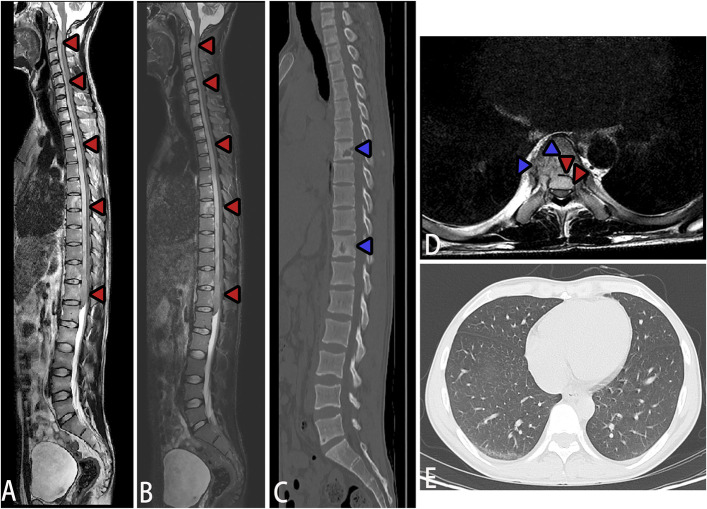

脊柱结核引起的脓肿通常发生在椎体的前部和外侧区域,常以冷脓肿的形式延伸至棘旁肌肉。虽然脊柱结核引起的椎管内脓肿很常见,但脊髓腹侧硬膜外腔纵向广泛脓肿的病例并没有很好的文献记载。该病的特点是发病隐匿,进展迅速,并具有不可逆转的神经损伤的高风险,突出了早期诊断和及时治疗的必要性。本文回顾了2例罕见的脊柱长节段结核性硬膜外脓肿,经过精确的手术干预和标准化的抗结核治疗,两例患者的症状均有显著改善。长节段结核性脊髓硬膜外脓肿(SEA)是一种非常罕见的并发症,可能导致严重的神经功能损害,磁共振成像显示广泛的脊髓硬膜外脓肿。临床表现,如颈部僵硬,容易被误认为结核性脑病;因此,建议使用增强MRI来鉴别SEA和结核性脑病。局部减压置管引流有助于保持神经功能,明确病因诊断,指导后续治疗。早期、充分和全面的抗结核治疗是成功管理的关键。

» Abscesses caused by spinal tuberculosis typically occur in the anterior and lateral regions of the vertebral bodies, often extending to the paraspinal muscles as cold abscesses. Although intraspinal abscesses due to spinal tuberculosis are very common, cases with longitudinally extensive abscesses in the ventral epidural space of the spinal cord are not well-documented. The disease is characterized by insidious onset, rapid progression, and a high risk of irreversible neurological damage, highlighting the necessity for early diagnosis and prompt treatment. » This review presents 2 rare cases of long-segment tuberculous spinal epidural abscesses, with both patients achieving significant symptom improvement after precise surgical intervention and standardized antituberculosis therapy. A long-segment tuberculous spinal epidural abscess (SEA) is an extremely rare complication that may cause severe neurological impairment, and magnetic resonance imaging revealed extensive spinal epidural abscesses. Clinical manifestations, such as neck stiffness, can easily be mistaken for tuberculous encephalopathy; therefore, contrast-enhanced MRI is recommended to differentiate a SEA from tuberculous encephalopathy. » Local decompression with catheter drainage can help preserve neurological function, establish a definitive etiological diagnosis, and guide subsequent treatment. Early, adequate, and comprehensive antituberculosis therapy is crucial for successful management.